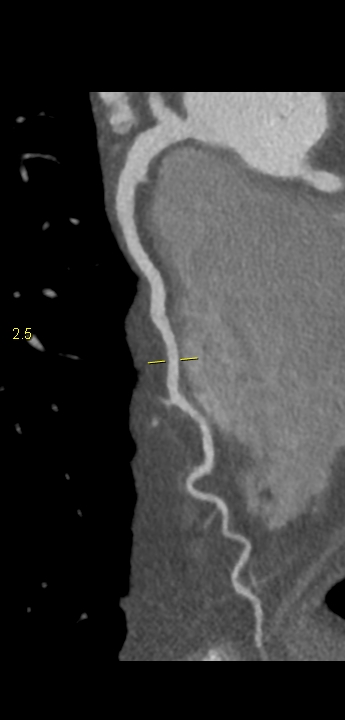

Figururile 1-9: reconstrucție în axul lung al vasului pentru arterele coronare cu evidențierea unui calibru global crescut la nivelul acestora și cu încărcătură ușoară-moderată de placă în principal calcificată

Discuţie caz nr 132: Examinările coroCT se efectuează în principal pentru aprecierea încărcăturii de placă precum și pentru evidențierea reducerilor de lumen ce necesită tratament. Această examinare a evidențiat creștere globală a calibrului arterelor coronare și o încărcătură ușoară-moderată cu placă în principal calcificată, fără a se evidenția arii de stenoză.

DE LUAT ACASĂ!!! Ectazia coronariană este o afecțiune rară caracterizată prin dilatarea anormală (diametrul vasului este de 1.5 ori mai mare) a arterelor coronare, care poate duce la afectarea fluxului sanguin și la un risc crescut de ischemie. Etiologia nu este cunoscută iar afecțiunea poate fi asociată cu ateroscleroză sau factori congenitali și reprezintă o provocare atât în diagnostic, cât și în tratament. Simptomele se suprapun adesea cu cele ale altor boli coronariene, ceea ce face ca identificarea timpurie să fie crucială. Opțiunile de tratament variază de la tratamentul medical cu terapie antiplachetară sau anticoagulantă până la proceduri intervenționale, cum ar fi angioplastia sau intervenția chirurgicală, în funcție de severitatea și riscul de complicații. Tratamentul pe termen lung se concentrează pe prevenirea evenimentelor ischemice și pe abordarea cauzelor care stau la baza acestora.